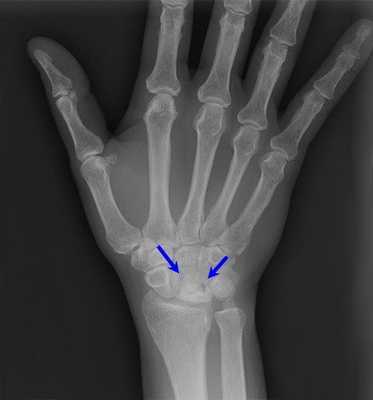

Рис. 1. Рентгенограммы кистевого сустава (слева в прямой проекции, справа — в боковой) при болезни Кинбека в стадии фрагментации: стрелками указана пораженная полулунная кость.

Решающим для установления диагноза является рентгенография, но при этом исследовании изменения полулунной кости можно обнаружить не ранее 2—3 мес. от начала заболевания. На рентгенограмме характерно изменение формы и повышение плотности тени полулунной кости. Тень ее приобретает неправильную треугольную форму, высота снижается, контуры кости остаются четкими, но неровными, волнистыми. В стадии фрагментации кость делится на различные по форме, размерам и плотности фрагменты (рис. 1), каждый из которых имеет неровные очертания. В III и IV стадии полулунная кость остается сплющенной, прилежащие отделы суставных щелей расширены. В дальнейшем происходит постепенное неполное восстановление рисунка структуры и формы кости. Полулунная кость остается деформированной, и по краям ее появляются губовидные костные разрастания. Подобные разрастания возникают и на смежных суставных поверхностях (V стадия). Суставная щель из расширенной становится суженной. В отдельных случаях в полости сустава выявляются внутрисуставные тела.

Изображение 3: Рентгеновский снимок правого запястья, показывающий болезнь Кинбека. Присутствует свернутая полулунная кость.

Рентгенограмма при болезни Кинбека.

Рентгеннограмма при болезни Кинбека